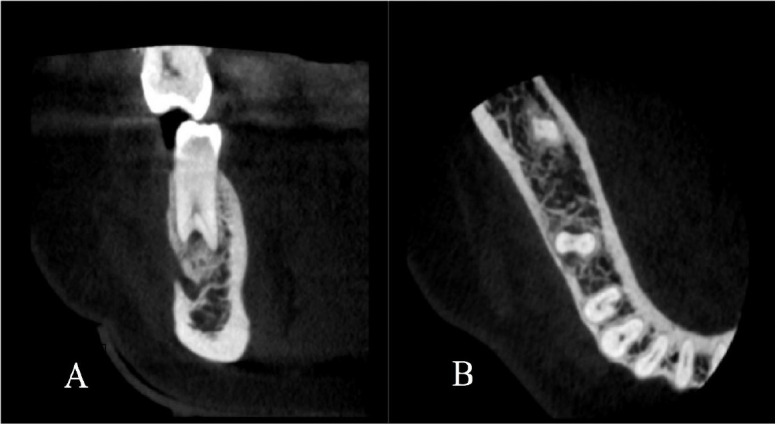

全面了解根管形态是成功进行牙髓治疗的关键。尽管有报道称下颌第二前磨牙的根尖通常只有一个根管,但在本病例中,我们却发现一颗下颌第二前磨牙有三个根管,而且形态呈陶土状。一名患者被转诊至马什哈德牙科学院牙髓科,主诉是下颌右侧第二前磨牙疼痛。牙髓坏死和慢性根尖牙周炎的诊断已经确定。最初的 X 光片显示她的前臼齿有两个牙根。然而,在锥形束计算机断层扫描的辅助下,确诊有三个根管。使用牙科手术显微镜成功地完成了根管治疗过程。使用锥形束计算机断层扫描和牙科手术显微镜极大地促进了牙齿形态的确定,并成功地进行了非手术根管治疗。

A complete understanding of canal morphology is essential to achieve successful endodontic treatment. Although mandibular second premolars are reported to have usually only one root canal at the apex, in this case we reported a mandibular second premolar with three root canals and taurodont morphology. A patient was referred to the endodontic department at Mashhad Faculty of Dentistry with a chief complaint of pain in her mandibular right second premolar tooth. The diagnosis of pulpal necrosis and chronic apical periodontitis was established. The initial radiograph showed a taurodont premolar with two roots. However, with cone-beam computed tomography assistance, three root canals were confirmed. The root canal treatment process was successfully managed with a dental operating microscope. Using cone-beam computed tomography and a dental operating microscope greatly facilitated the determination of tooth morphology and successful following nonsurgical endodontic treatment.